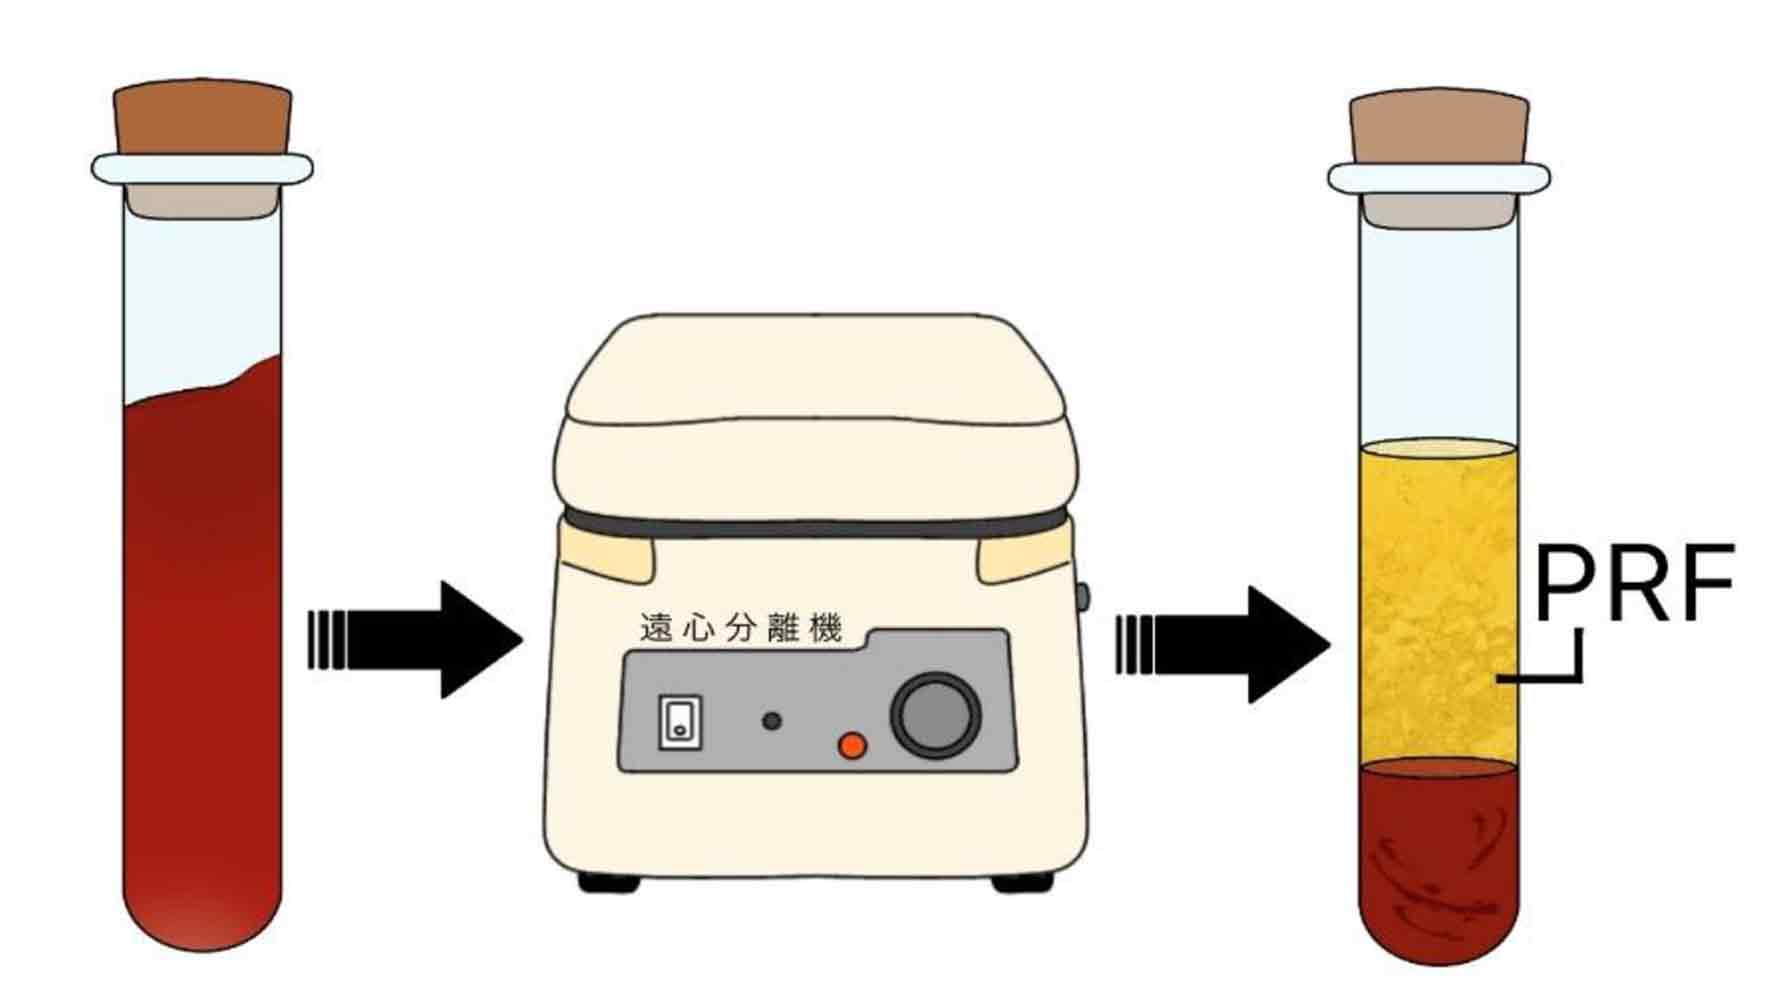

再生医療

股関節の再生医療は、PRP注射・APS注射という大きく2つに分類されます。PRP注射・APS注射とは、自身の血液中から採取した成分を、股関節の損傷部位に注入する治療法です。注入された成分には成長因子が含まれており、軟骨や関節の再生を促す効果が期待されます。